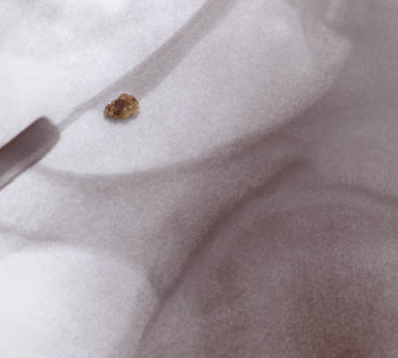

요로 결석은 요로계(신장, 요관, 방광, 요도)에서 결석이 형성되는 질환으로, 비뇨기계 질환 중 가장 흔한 것 중 하나입니다. 요로 결석은 신장에서 나온 요소들이 모여 결정되어 결석을 형성하고, 이 결석이 요관을 통과하려 할 때 발생하는 통증으로 증상을 나타내며, 요관 통과 과정에서 출혈 등의 합병증이 생길 수 있습니다. 요로 결석은 소변에서 나오는 성분의 양과 질에 따라 발생할 수 있으며, 당뇨병, 고혈압 등의 질환과 관련되어 있습니다.

요로 결석의 증상은 결석 크기, 위치, 상태, 개인의 건강 상태 등에 따라 다양하게 나타납니다. 대부분의 경우, 결석이 작으면 자연적으로 배출되거나 약물 치료를 통해 치료됩니다. 하지만, 결석이 크고, 자연 배출이 어려울 경우에는 내시경적 수술이나 초음파 치료 등의 치료가 필요할 수 있습니다. 따라서 요로 결석 증상이 나타날 경우, 적절한 치료를 받기 위해 전문의의 진단과 조언을 받는 것이 중요합니다.

요로 결석의 치료 방법은 결석의 크기, 위치, 상태에 따라 다양합니다. 일반적으로, 작은 결석이면 자연 배출이 가능하고 약물 치료를 통해 치료할 수 있습니다. 그러나, 큰 결석이나 발생 위치가 위험한 부위에 위치한 경우에는 내시경적 수술이나 초음파 치료 등의 치료 방법이 필요할 수 있습니다.